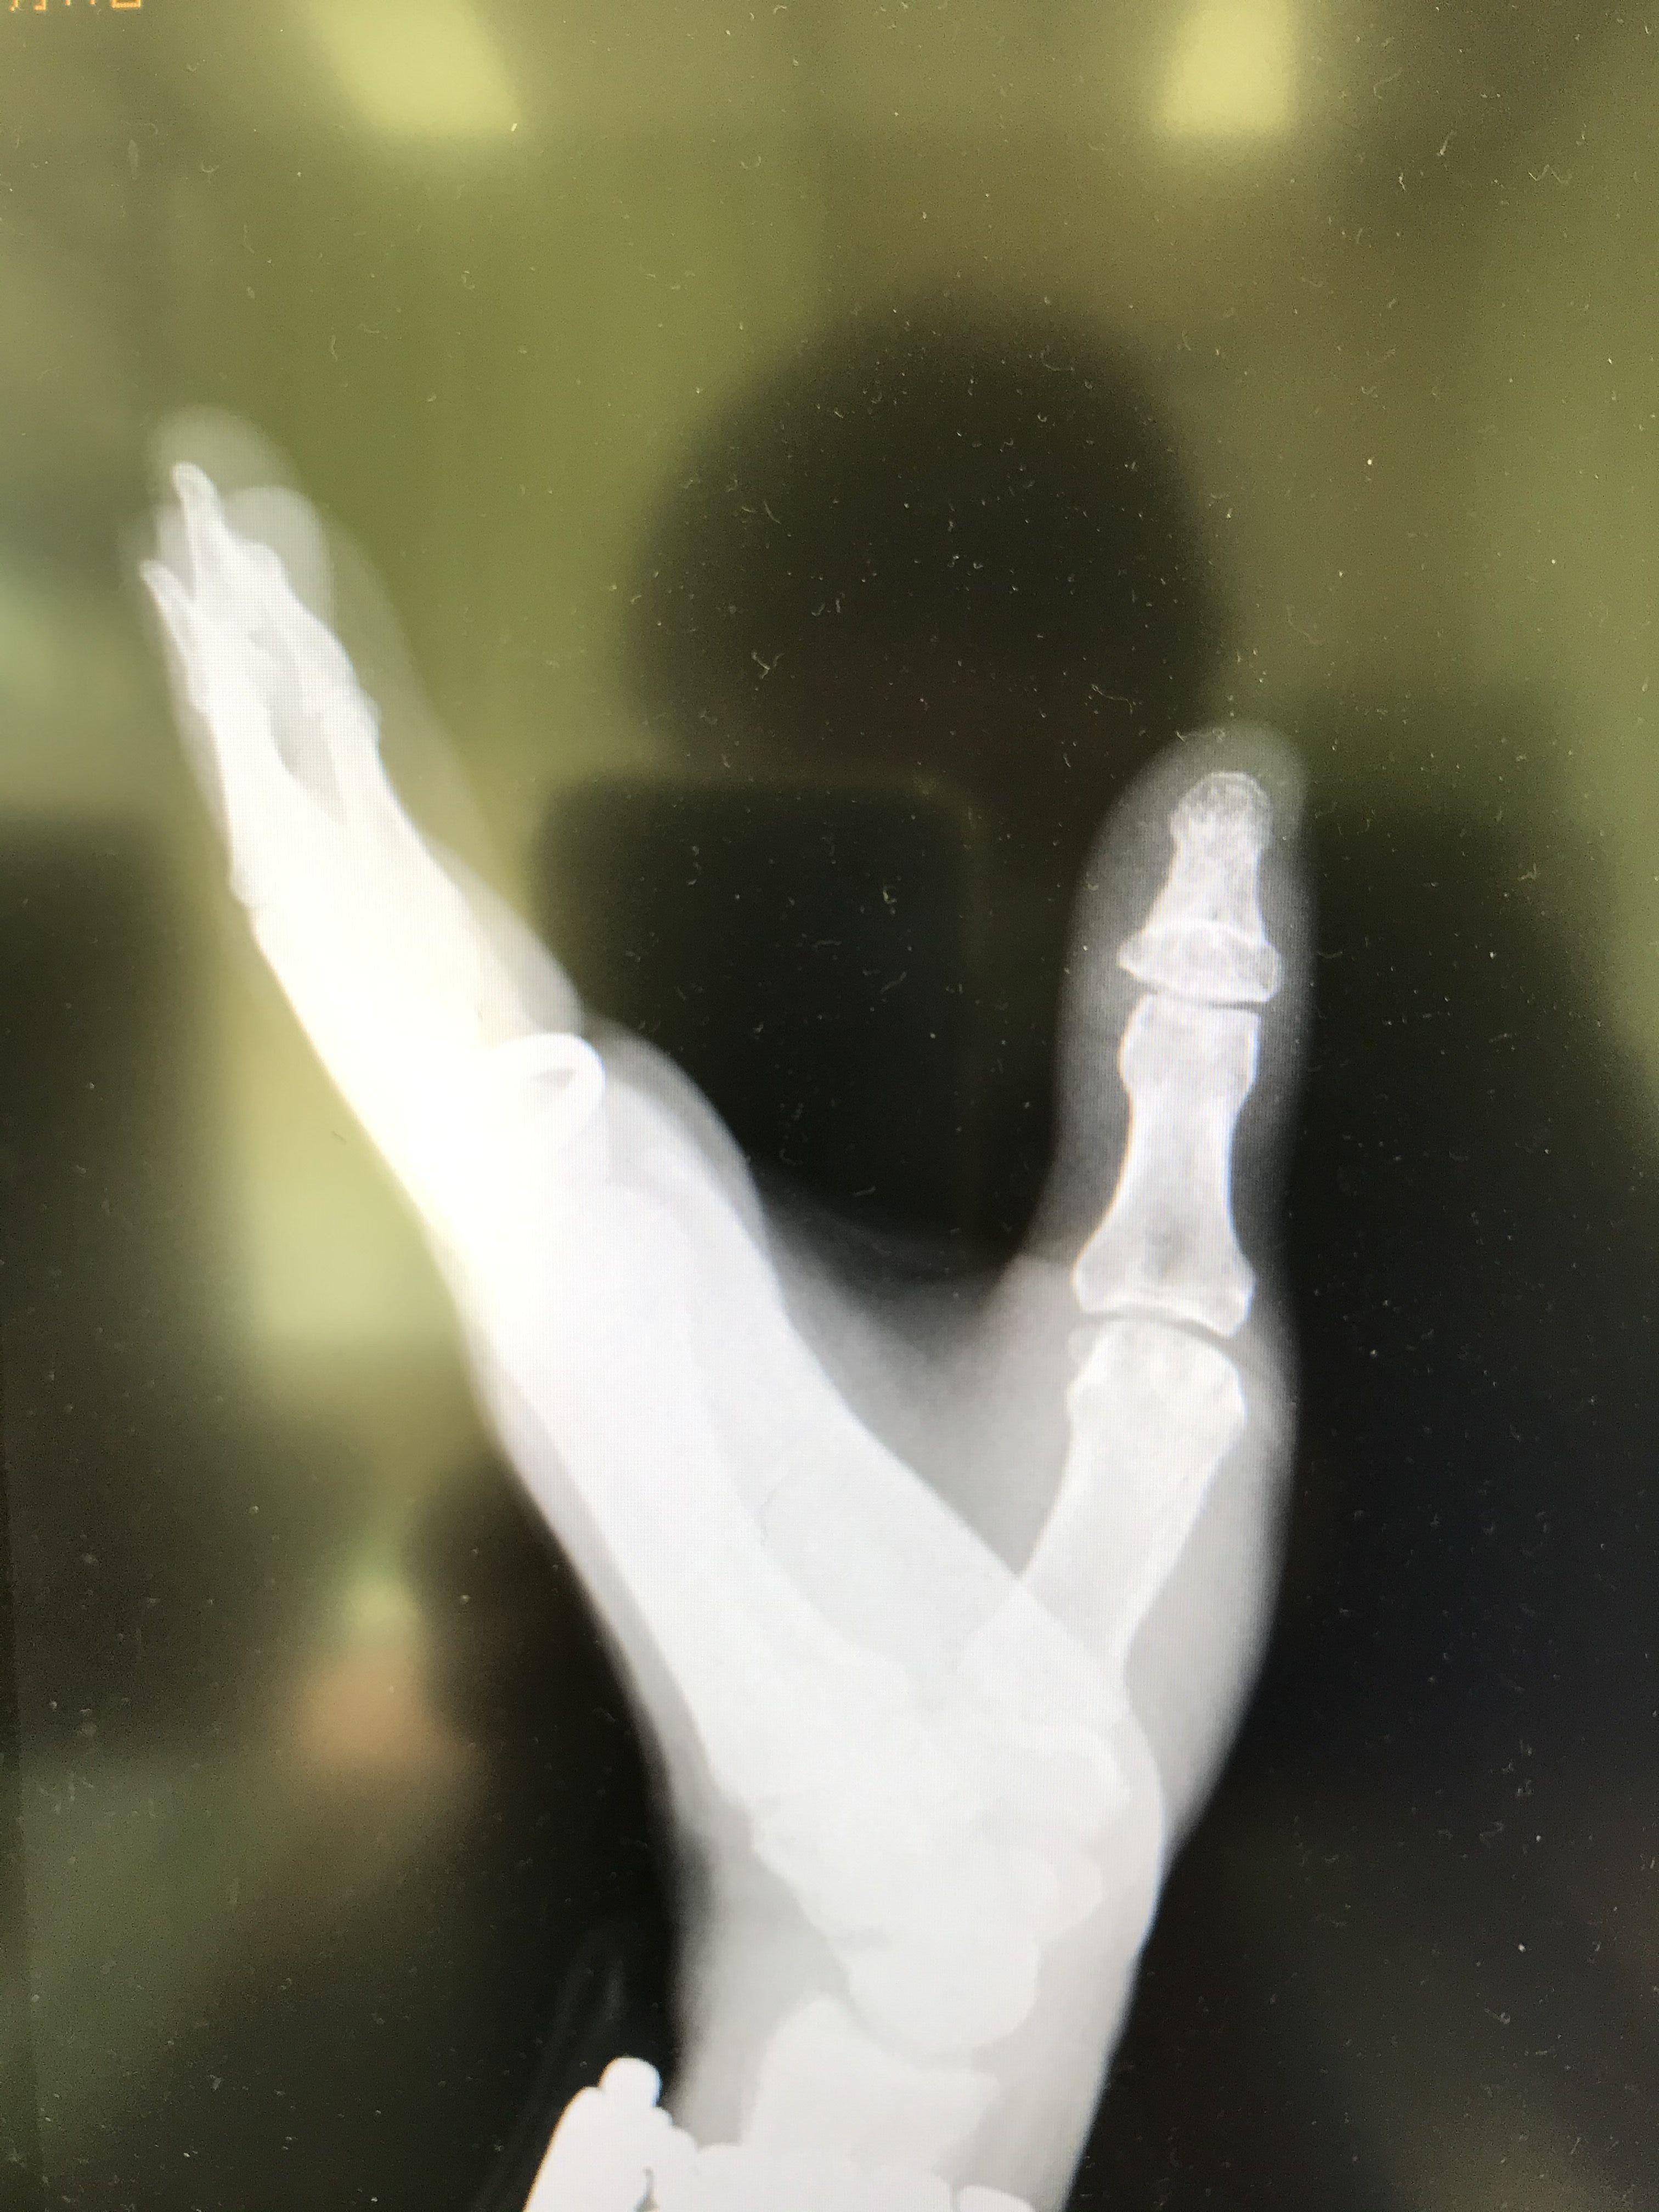

今日 12/23 久し振り 病院 に行き…クール

レントゲン を撮りました♪スマイル

は付いてる様ですが…しょんぼり

右手 ほど曲がりません...号泣